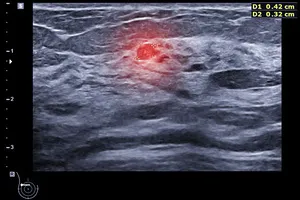

11. 유방 질환

유방은 호르몬 변화에 민감하게 반응하는 기관으로, 다양한 질환이 발생할 수 있습니다. 유방 낭종, 유선염, 섬유종 등은 물론, 유방암과 같은 심각한 질환도 유발될 수 있습니다. 이러한 유방 질환들은 흔히 압통이나 통증을 유발합니다. 특히 오른쪽 가슴에 통증이 느껴진다면, 유방 질환을 의심해 보고 정확한 진단을 위해 유방 초음파, MRI, 조직 검사 등을 받아보는 것이 좋습니다.